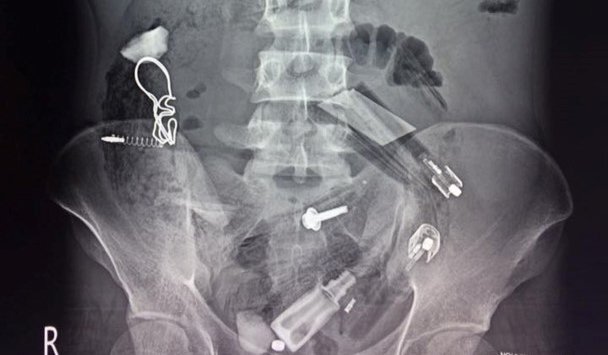

Khi phẫu thuật, các bác sĩ phát hiện hơn 30 dị vật như bút bi, bật lửa, túi nilon,... trong bụng một bệnh nhân nghi sử dụng ma túy đá.